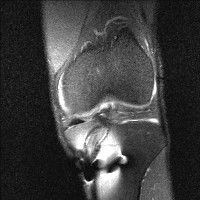

무릎 mri 간단히 봐주실 수 있으시나요 ㅠㅠ

안녕하세요 8년전 십자인대 수술하고 최근 무리한 운동에 무릎 불편감이 생겨서

mri 찍었습니다.

진단결과는 첫 찍은 병원에서 활액막염 이라는 진단을 받았습니다. 혹시 봐주실 수 있으실까요?

올라온 MRI가 단편적이라서 정확한 진단에 어려움이 있지만 십자인대에는 큰 이상이 있지는 않은것 같으며, 무릎관절내 물이 있는 것으로 보아 활액막염의 진단이 맞을 것 같습니다.

하지만 단편적인 영상이기 때문에 촬영병원에서 정확한 판독지 등을 받으시는 것이 좋겠습니다.